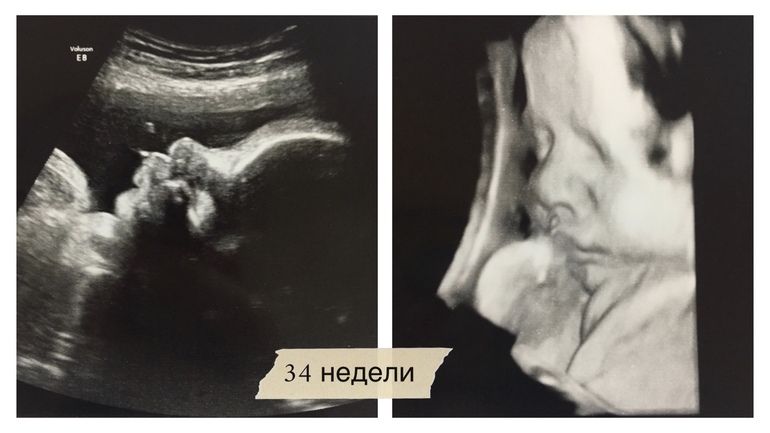

34 недели, фотки с УЗИ ❤️ И я сегодня молодец!

Девчуля моя плескается в животе аки русалка: пока делали УЗИ, она крутилась из поперечного в тазовое. Вод, по словам врача, более чем достаточно. Многоводия нет, но на моем сроке их обычно поменьше.

Сделали несколько фотографий:

Все УЗИ девочка моя хмурилась и пинала датчик, чем веселила врача 😁